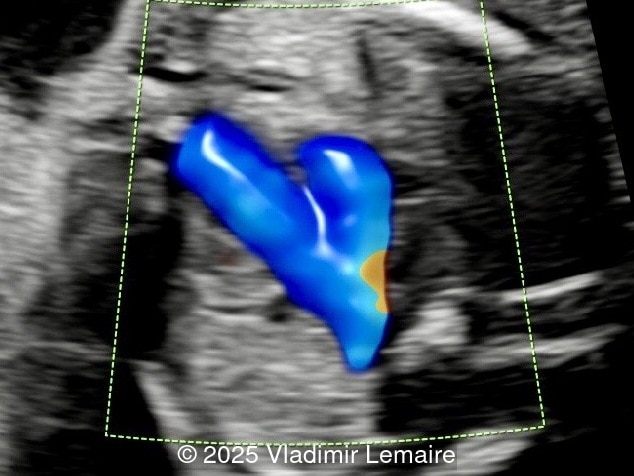

We present a case of isolated tricuspid atresia type 1 with persistent left superior vena cava. No other extracardiac anomalies were found. Our diagnosis was confirmed after birth.

In the images below, the abbreviations are as follows: RA: right atrium; RV: right ventricle; LV: left ventricle; MV: mitral valve; LA: left atrium; FO: foramen ovale; SVC: superior vena cava; LSVC: left superior vena cava; PV: pulmonary veins; PA: pulmonary artery; MPA: main pulmonary artery; RPA: right pulmonary artery; AO: aorta; dAO: descending aorta; aAO: ascending aorta; DA: ductus arteriosus; T: trachea; * marks the ventricular septal defect.

Color Doppler confirms the diagnosis on grayscale ultrasound, as it demonstrates the lack of blood flow across the tricuspid valve and a patent mitral valve. Due to increased blood flow across the mitral valve, aliasing is typically noted on color Doppler. Mitral valve regurgitation has been associated with a poor outcome. The right ventricular cavity is filled in late diastole from the left ventricle, through the ventricular septal defect. Left-to-right shunting across the ventricular septal defect can be seen on color Doppler. Color Doppler is helpful in the evaluation of flow across the great arteries. Flow across the pulmonary artery is generally antegrade. Pulmonary stenosis should be suspected when the vessel is diminutive in size rather than the demonstration of turbulent flow on color Doppler, which is typically absent in these cases.